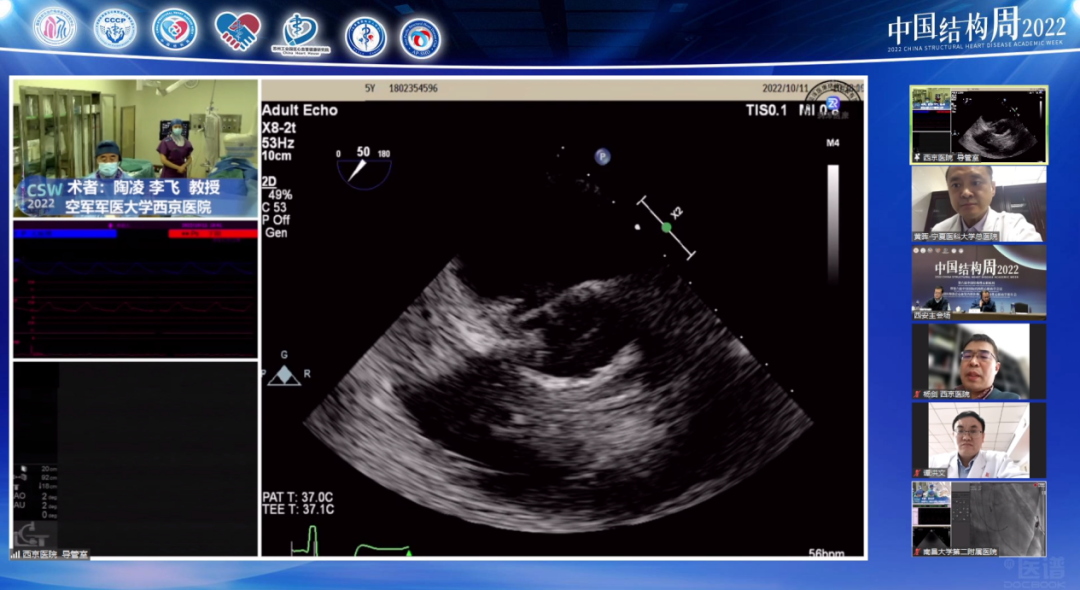

空军军医大学西京医院陶凌教授团队(术者:李飞教授)带来一例感染性心内膜炎重度AS患者。

针对本例患者,术者团队介绍了特殊情况,食道超声检查示无冠窦窦壁有囊性结构,考虑存在感染,血流通过无冠窦窦壁喷射到囊腔里面,随后询问病史患者自述有泌尿系感染1月余,故考虑合并感染性心内膜炎,囊性结构是陈旧性赘生物。有专家认为患者有脑梗死病史2月余,系囊性赘生物脱落所致。

与会专家针对食道超声发现的囊性结构展开激烈探讨,对于泌尿系感染和脑梗死的病因认为是赘生物脱落所致,在此情况下,建议该患者不太适合TAVR手术。李飞教授同意现场探讨内容,下一步策略计划再次评估CTA,局部采血后血培养,核磁明确,考虑到患者心衰严重,首先保守治疗后,选择SAVR(外科主动脉瓣置换术)还是抗炎后TAVR具体情况深入分析后在做抉择。但有专家更倾向于外科开胸换瓣,可以进一步分析病理。